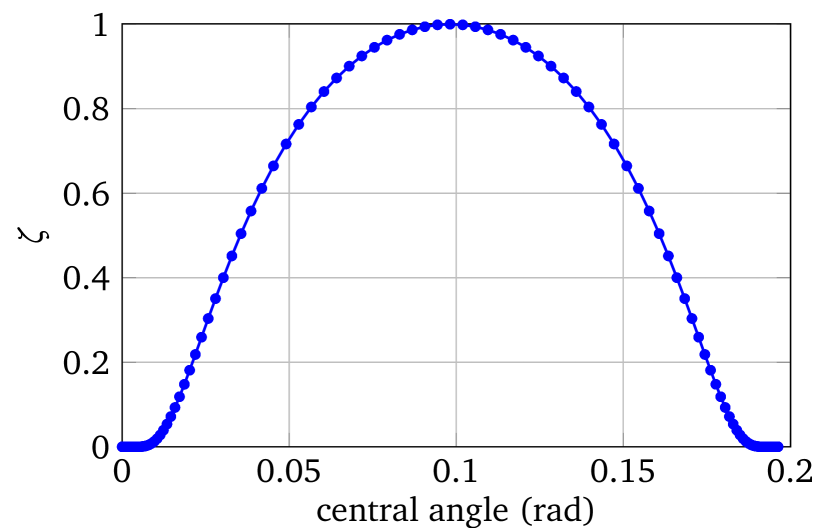

To simulate the power density , SCEM is used to yield better regularity of the electrical potential. The electrode conductance of is chosen as

Here, is the length of the electrode, which is proportional to the central angle corresponding to the electrode. is then scaled to have the required maximum value. The distribution of for the calculation in this paper is given in Figure 3(a) with a maximum value 1. The power density simulated with SCEM is given in Figure 3(b) for a region near one electrode. Here, the current pattern is . A smooth distribution of near the edge of the electrode is observed. For the same region, the power density simulated from CEM is also given in Figure 3(c) with for . Two singularity points are observed at the edges of the electrode. These singularities will cause instability in the reconstruction, and therefore SCEM is used in LM-SCEM.